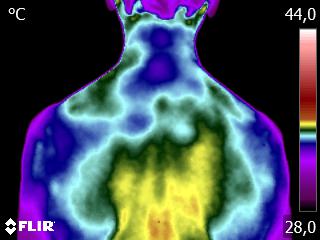

Como no caso do termograma apresentado, de um paciente do sexo masculino, 79 anos, com múltiplas comorbidades, que apresentava dor torácica e cervical. A Análise Termofuncional evidenciou alterações térmicas compatíveis com o quadro clínico, respeitando a individualidade biológica e o contexto global do paciente.

Essas informações não configuram diagnóstico médico, mas qualificam a avaliação funcional, fortalecendo o raciocínio clínico e promovendo profissionalismo no desfecho do caso.

A termografia, aplicada dentro da técnica Termofuncional, não é método diagnóstico isolado, mas um método complementar de análise funcional, dentro das atribuições legais.